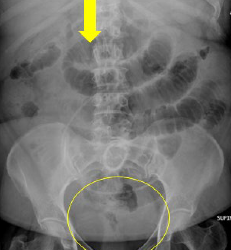

Pathology?

pneumoperitoneum (free intraperitoneal air)

causes: rupture of hollow viscus, ulcer, tumor, trauma, instrumentation, post-operative (expected up to 5-7 days), necrotizing enterocolitis (neonatal setting)